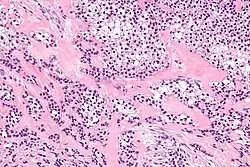

| Micrograph of a hyalinizing clear cell carcinoma showing the characteristic clear cells and surrounding hyalinized stroma. H&E stain. | |

HCCC consist of cells with abundant clear cytoplasm, arranged in cords, trabeculae or clusters in a hyalinized stroma.[3] Nuclear pleomorphism is usually minimal and mitoses are infrequently seen.[2]

Owing to their glycogen content, which explains the "clear" appearance under the microscope, tumour cells stain with PAS. Immunostains for S100 and smooth muscle actin (SMA) are typically negative, but positive for cytokeratins and epithelial membrane antigen (EMA).